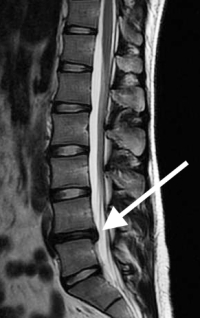

(Click to Enlarge Image) Normal midline (sagittal) MRI. Note the high signal (white) within the disc space (arrows) indicating good hydration of the nucleus. Disc space is also tall.